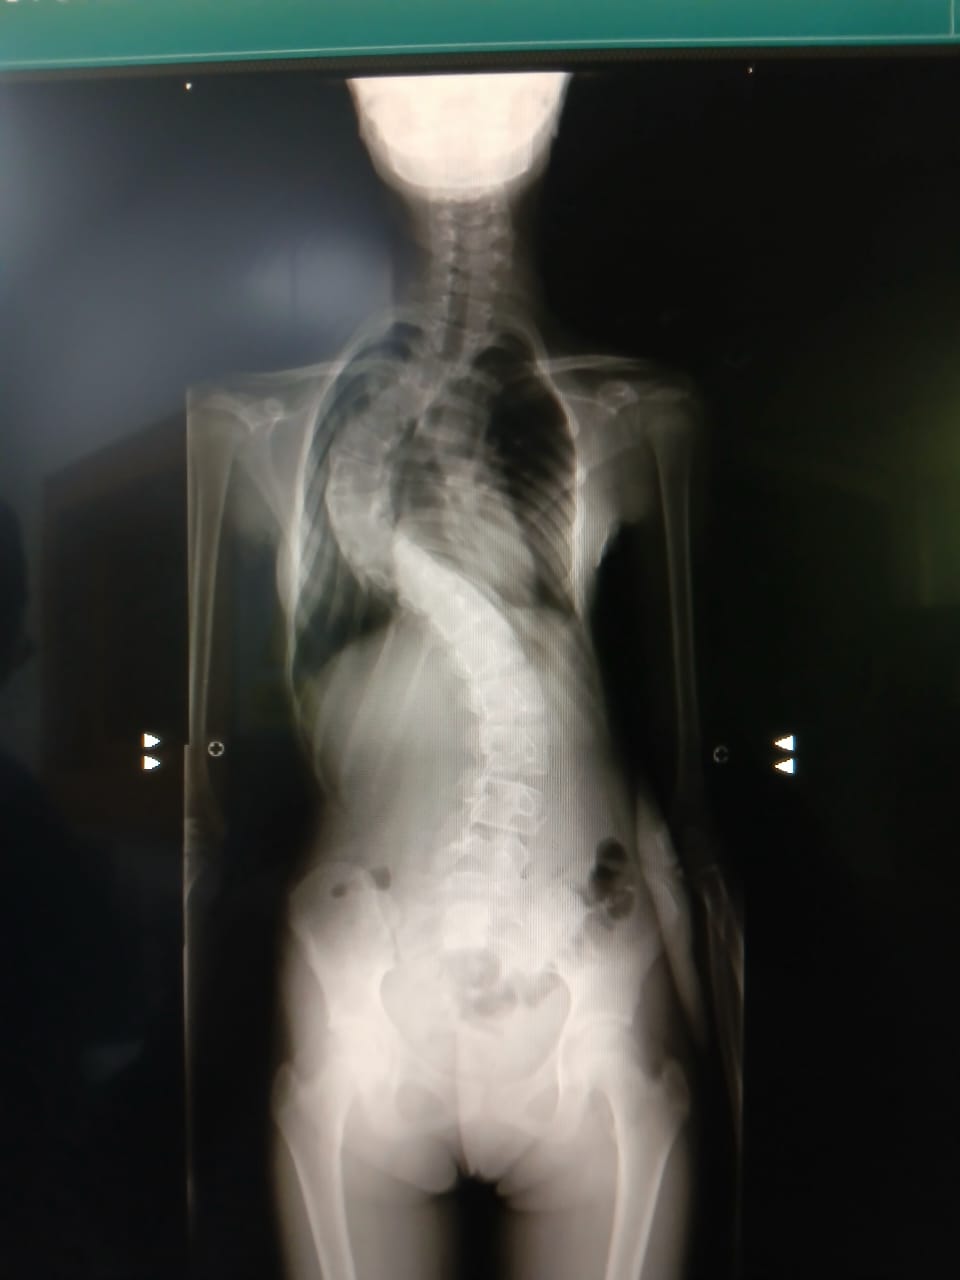

La pequeña Victoria Chiquinquirá Viera Weffer, una hermosa niña marabina de 11 años, fue diagnosticada desde los 3 años con escoliosis, es decir, una curvatura lateral anormal en forma de S de la columna vertebral.

Viera, descrita como una “niña inteligente que ama bailar y nadar”, posee una curvatura de 86 grados, más precisamente una escoliosis neuropática severa, lo que hace que su condición médica sea delicada.

La operación, cuyo costo es de 38.281 dólares, es sumamente necesaria, pues la escoliosis está “moviendo la caja torácica”, por lo que “su pulmón derecho no tiene suficiente espacio para trabajar bien”.